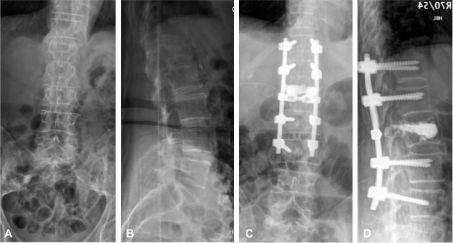

Figure 3. Fracture de L1 traitée par réduction et arthrodèse postérolatérale associée à une expansion vertébrale (kyphoplastie). Bilan préopératoire de face (A) et de profil (B). Bilan postopératoire de face (C) et de profil (D).